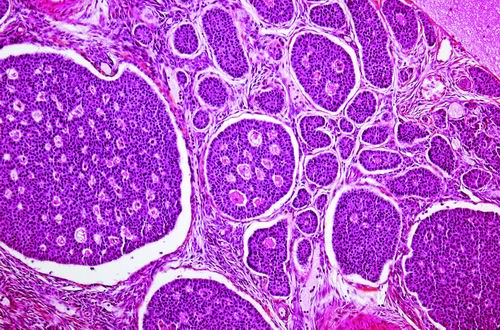

一项临床试验将对卵巢癌细胞进行改造,并将这些细胞重新输给患者。图片来源:PJD/SCIENCE SOURCE

本报讯 在全球部分地区,捐献的血液或血小板等血液成分在输注给患者之前,会用紫外线和核黄素进行消毒。这种名为Mirasol的技术能够消灭多种病毒、细菌和寄生虫。如今,研究人员打算用这种方法对付癌症,即先灭活肿瘤细胞,再将其重新输入患者体内,从而引发有益的免疫反应。他们已在小鼠和狗身上进行了实验,并计划在卵巢癌患者中进行第一阶段试验。

研发这款抗癌疫苗的灵感源于Goodrich的一个发现:白细胞经过Mirasol技术处理后,虽然失去了生物活性,但结构却完好无损。他推测,将患者癌细胞用同样方法制成“细胞僵尸”并输回体内,或许能引发对肿瘤的免疫反应。团队得出结论,这种疗法安全性较高,因为经紫外线处理的癌细胞无法分裂增殖,不会形成新的肿瘤。

由光子制药公司赞助的一项临床试验将在美国希望之城国家医疗中心启动,计划招募8名复发性卵巢癌患者。研究人员会将切除的肿瘤细胞与核黄素混合并进行紫外线照射,再加入一种名为“佐剂”的免疫增强剂,定制疫苗。患者将接受3次疫苗注射,研究人员会密切监测不良反应,评估免疫应答水平。